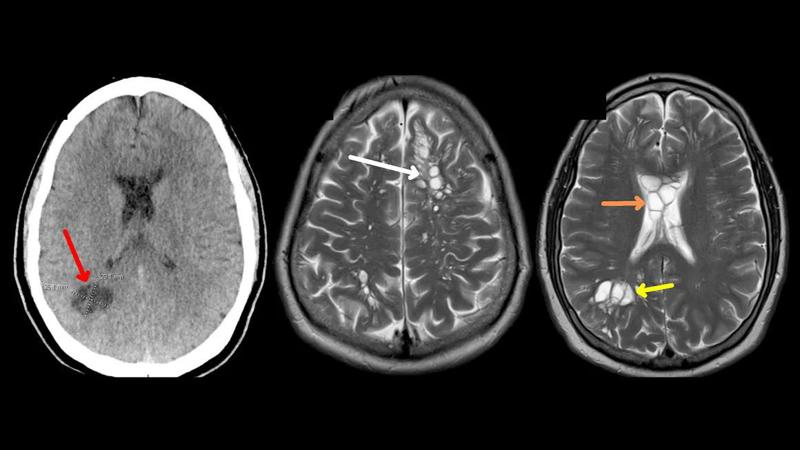

ექიმმა მას კომპიუტერული ტომოგრაფია ურჩია, შედეგად თავის ტვინში მრავლობითი კისტა აღმოჩნდა, თავდაპირველად ფიქრობდნენ, რომ ეს იშვიათი ნევროლოგიური მდგომარეობა უნდა ყოფილიყო, რომელსაც თანდაყოლილი ნეიროგლიური კისტა ეწოდება.

ლაბორატორიული კვლევის შედეგად დადგინდა, რომ თავის ტვინში არსებული კისტა, სინამდვილეში პარაზიტული ჭიის ლარვები იყო. ამან ინფექცია გამოიწვია, რომელსაც ნეიროცისტიცერკოზი ეწოდება.